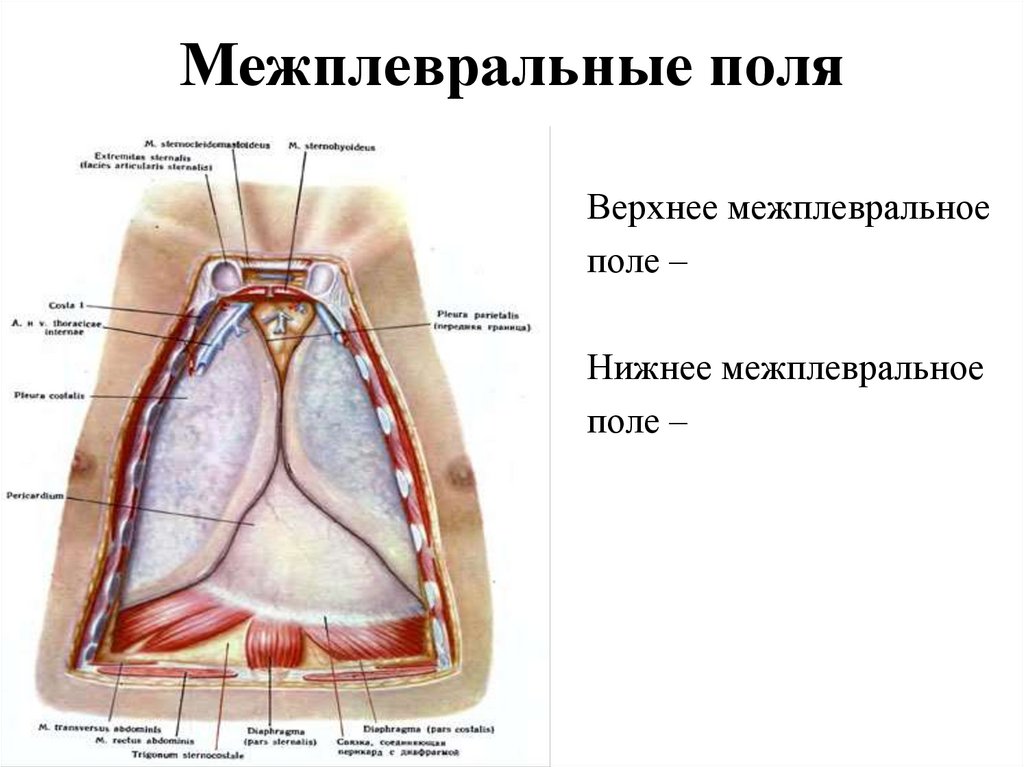

Анатомия Сердца: Расположение и Функции